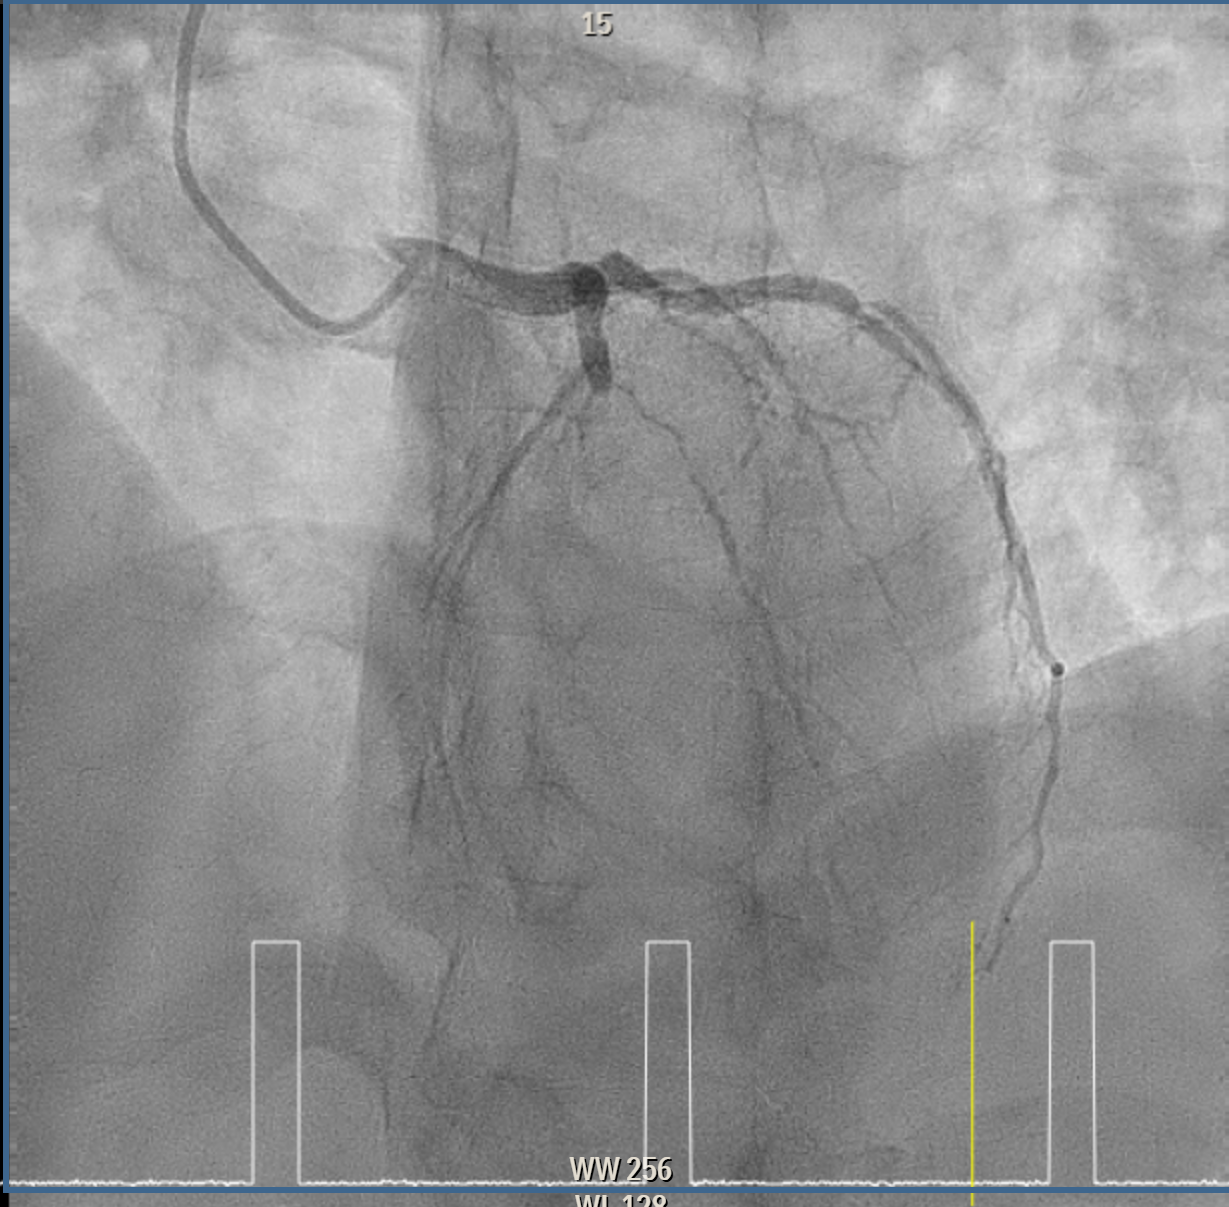

Coronary intervention was performed on a proximal LAD (pLAD) total occlusion via single right radial approach using 6F XB 3.5 guiding catheter. Initial antegrade attempts with RunThrough Floppy and Fielder-XT wires were unsuccessful due to buckling against the proximal cap. Wire strategy was escalated to Gaia Second wire with Finecross microcatheter support, allowing careful penetration of proximal cap and subsequent advancement through distal cap. True lumen position was confirmed with contrast injection through the microcatheter, and wire was then exchanged to a Fielder-XT wire to safely navigate to distal LAD (dLAD) and reduce risk of perforation. Lesion preparation was performed with stepwise predilatation, beginning with Sapphire 0.85 ¡¿ 5 mm balloon at 10–12 atm in pLAD to dLAD. Further predilatation was performed with Sapphire 2.0 ¡¿ 15 mm balloon at 12 atm from dLAD to mid LAD (mLAD) and higher pressure up to 16atm at pLAD. Despite multiple inflations, pLAD remained tight, prompting escalation with a Sapphire 2.5 ¡¿ 15 mm balloon at up to 18 atm and Scoreflex NC 3.0 ¡¿ 15 mm balloon at 8–12 atm to adequately prepare mildly calcified pLAD segment. Final predilatation achieved optimal luminal caliber. DCB was then performed, with m-dLAD treated using Magic Touch 2.25 ¡¿ 35 mm and the p-mLAD treated with Magic Touch 3.0 ¡¿ 40 mm. Both were deployed at 8 atm for 60 seconds. The procedure resulted in excellent luminal gain with no residual stenosis, recoil, or perforation.